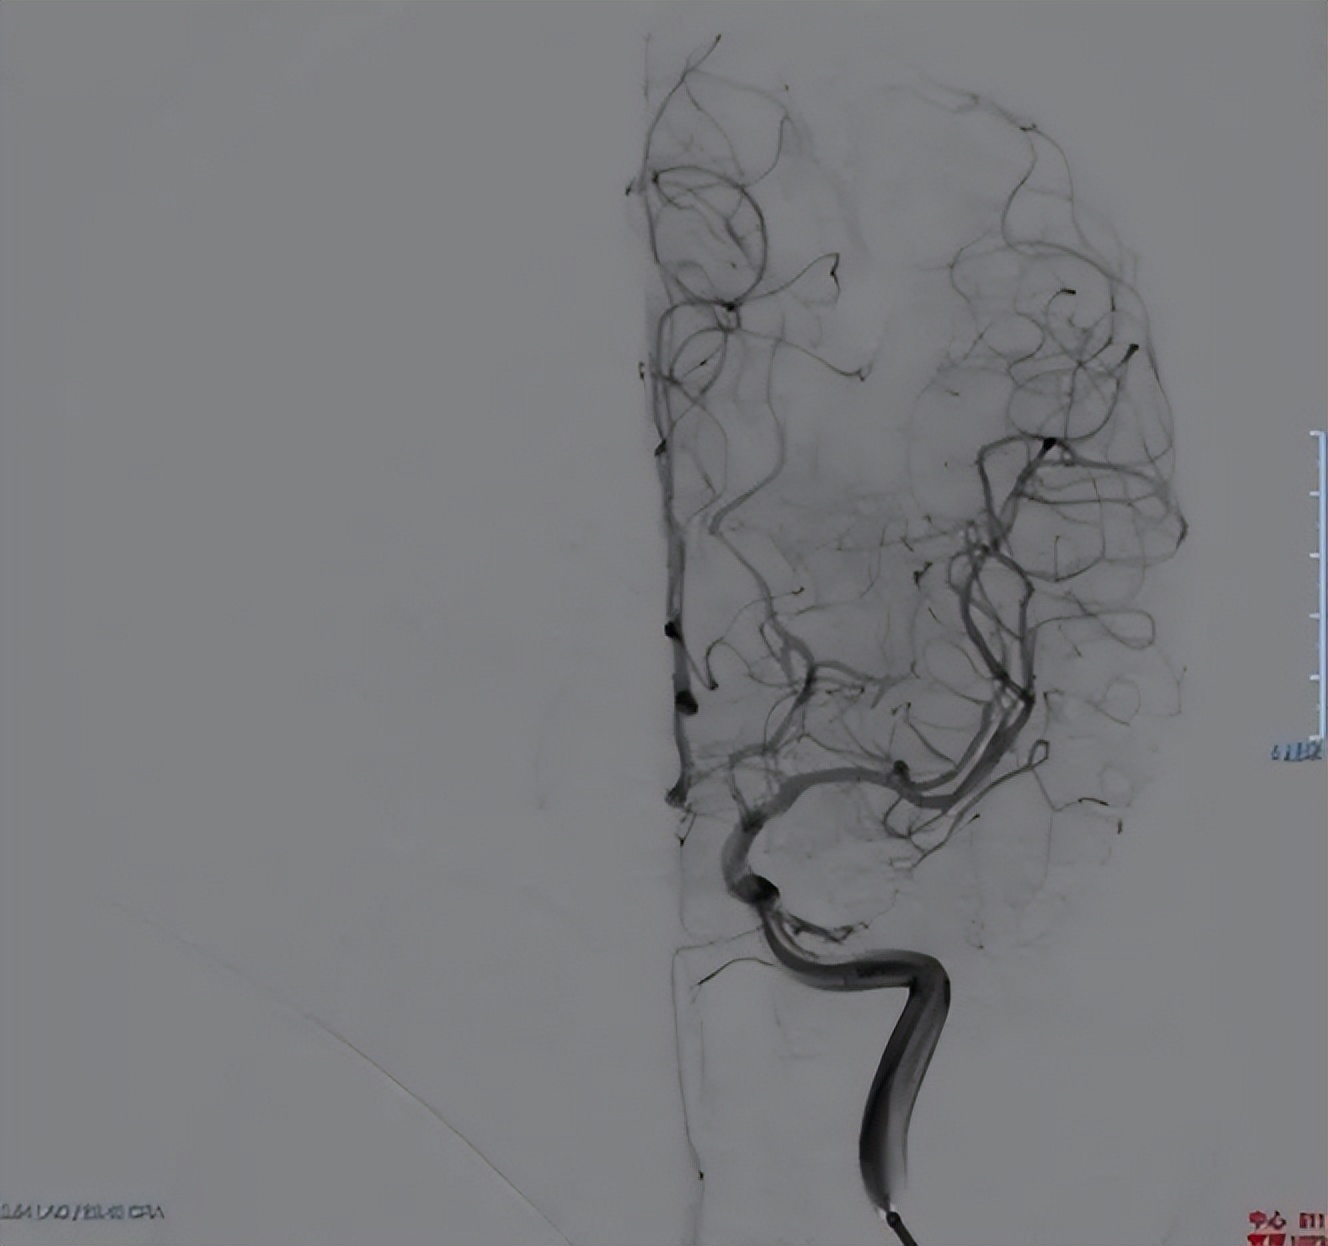

正是术前精准评估、术中精确操作的*管双**齐下,王女士的脑血流得以顺利恢复正常。后经3个月康复锻炼,她右侧肢体活动基本恢复,期间无脑梗塞发作,再次复查脑血管造影,原先狭窄的脑血管也已经恢复到正常管径。“听说得了脑血管方面的毛病,都会留下点后遗症。我非常感恩医生们的努力,把妈妈‘完整无缺’地还给了我!”王女士的女儿感激地表示。

术后复查的DSA↑